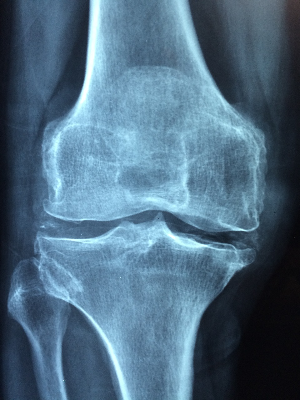

교원병이란 본래 자신의 몸을 지켜야 할 면역체계에 이상이 생겨 자신의 몸을 공격해 버리는 '자가면역질환' 질병을 총칭합니다. 교원병 중에서도 많은 '류머티즘 관절염'이나 전신의 여러 장기에 염증이 생기는 '셰그렌 증후군', 젊은 여성에게 많은 '전신성 에리테마토데스' 등이 있습니다. 류머티즘 관절염은 관절에 염증이 일어나 통증과 변형이 생기는 질환입니다. 염증이 진행되면 뼈가 파괴되면서 관절의 변형을 일으키게 됩니다. 그렇기 때문에 심해지면 일상생활에도 큰 지장을 초래하게 됩니다. 일본에서 70만 명 이상의 환자가 있는 것으로 알려져 있습니다. 이전에는 류머티즘 관절염에 대한 효과적인 약이 없었기 때문에 관절의 변형을 억제하지 못하고 와병으로 이어지기도 했습니다. 그러나 현재는, 조기 발견·조기 치료에 의해, 병이 침착하고 안정된 상태인 「관해」로 이어지는 경우도 증가하고 있습니다. 남성보다 여성에게 더 많이 나타나며, 30~50대에서 발병이 많은 것이 특징입니다. 류머티즘 관절염이 심하지 않으려면 조기 발견·조기 치료가 중요합니다. 다음에 언급할 만한 증상이 없는지 확인을 해 보도록 합시다. 특히 아침에 뻣뻣함은 류머티즘 관절염의 전형적인 증상입니다. 또한 관절의 붓기나 열이 나는 것도 염증의 사인이 되는 중요한 포인트입니다. 몇 가지 해당되는 경우는 의료 기관에서 자세한 검사를 받는 것을 추천합니다. 류머티즘 관절염을 진단하려면 자세한 검사가 필요합니다. 문진과 촉진을 한 후 혈액 검사에서 염증과 면역 이상의 유무와 그 정도를 조사합니다. X선 검사는 뼈의 파괴나 관절의 변형을 조사하는 데 효과적이지만, '관절 초음파 검사'는 관절을 감싸는 활막이라는 얇은 막의 염증 상태까지 확인할 수 있습니다. 이전에는 류머티즘 관절염에 대한 효과적인 약은 없었습니다. 그러나 현재는 염증이나 염증의 원인이 되는 면역의 이상을 일으키기 어렵게 하는 약이 차례차례 등장하고 있습니다. 뼈의 파괴가 진행되기 전부터 치료를 시작함으로써 변형을 방지하고 관해를 유지할 수 있습니다. 치료의 중심을 담당하는 것은 항류머티즘제인 '메토트렉사트'입니다. 세계적으로 류머티즘 관절염의 첫 번째 선택 약이 되고 있으며, 일본에서도 약 80%의 환자가 복용하고 있습니다. 메토트렉사트는 관절의 염증을 일으키는 면역 세포 등의 기능을 억제하고 류머티즘 관절염의 진행을 억제합니다.